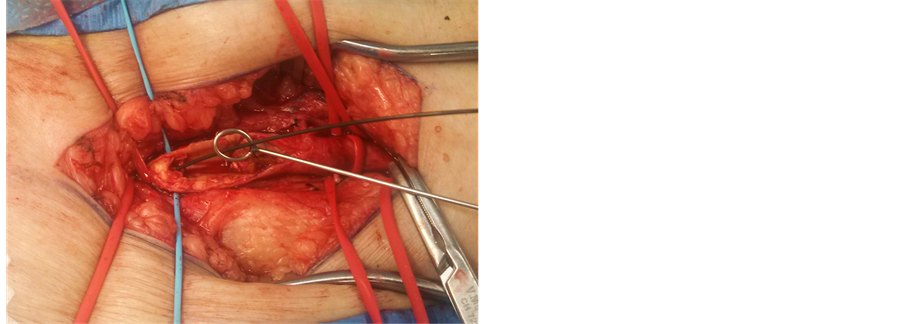

Isolation of the common femoral, superficial femoral, and profunda arteries was first carried out. A guidewire was placed distally and kept there throughout the procedure (Figure 1). Remote endarterectomy was then carried out using a Vollmar Ring Dissector [LeMaitre Vascular] (Figure 2). A Viabahn stent (GORE VIABAHN

Figure 1. Exposure and arteriotomy of the CFA with guidewire placement.